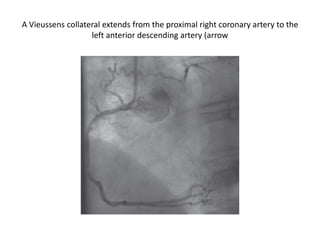

A Vieussens collateral extends from the proximal right coronary artery to the

left anterior descending artery (arrow